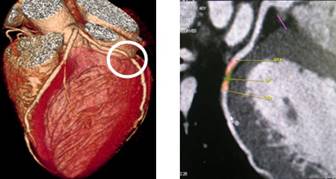

心脏及冠状动脉:

高分辨冠状动脉软斑块和支架